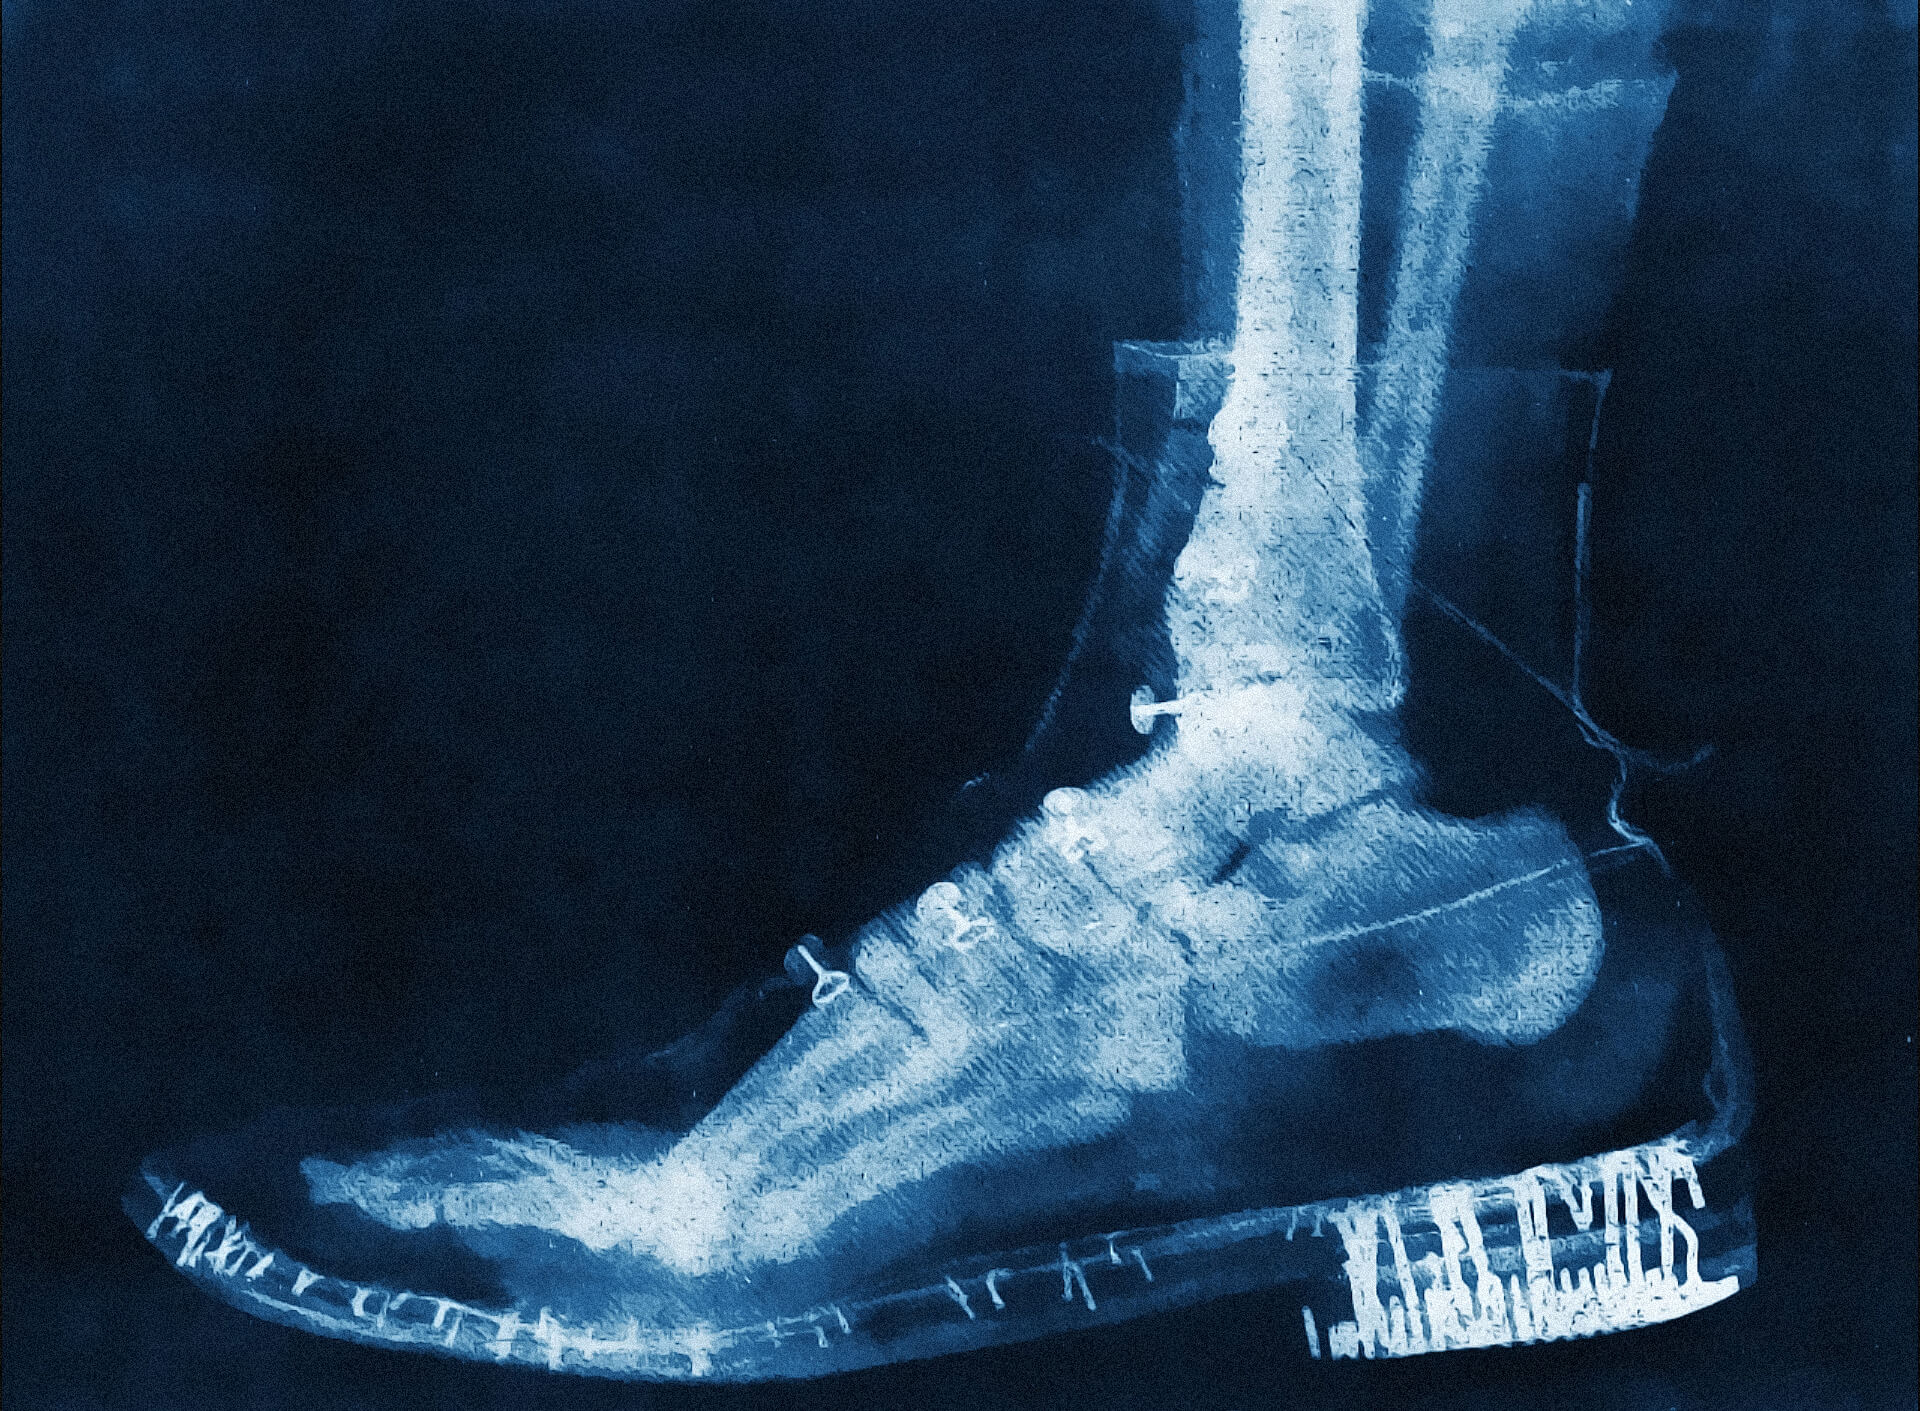

Early X-ray of a foot inside a shoe

By M. Nardi, after Arthur Honoré Radiguet (1850–1905)

No. 2045 Musée Radiographique Radiguet

Arthur Honoré Radiguet was a French physicist, engineer, optician,

and photographer known for his groundbreaking work in developing

scientific instruments, including early X-ray equipment. Building on

his family’s legacy in optics and specialising in microscopes and

loupes, he founded the company Radiguet et Massiot, which produced

devices for radiography—an emerging field inspired by Wilhelm

Röntgen's discovery of X-rays in 1895. In 1896, Radiguet became a

leading French manufacturer, distributor, and photographer of X-ray

technology, compiling his creations into the Musée Radiographique

Radiguet. Early experiments with this technology, such as his X-ray

of a foot inside a shoe, likely created for scientific demonstration

or educational purposes, demonstrated its ability to penetrate

materials and reveal internal structures. Despite his remarkable

contributions, Radiguet's dedication came at a personal cost, as

radiation poisoning ultimately claimed his life in 1905. Despite the

tragic end, Radiguet's contributions remain vital, earning him

acclaim as a pioneer of French radiography and leaving behind

invaluable X-ray photographs as testaments to a transformative era

in scientific history.